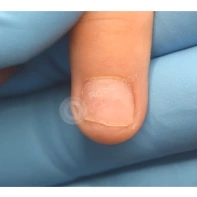

04. Ноготь после удаления хирургом начал врастать не в бок, как было раньше, а спереди, он как бы упирается в кожу, а не ложится сверху, когда отрастает. Это тоже считается вросшим? Или лечится как-то иначе?

В вопросе, скорее, речь идет о синдроме оплывшего дистального валика, что является проявлением ониходистрофии, и может появляется после отслоения ногтевой пластины на фоне длительного давления или травмы, а также после длительного отсутствия ногтевой пластины после ее удаления. В таком случае ногтевое ложе остается частично не прикрытым, и кожа дистальной части околоногтевого валика, накрывает оголенное ложе. Тем самым ногтевая пластина, отрастая, встречает «преграду» в виде валика и травмирует его.

В данном случае необходима чистка ногтевой пластины и установка коррекционных систем. Иногда подолог может установить тампонады или протезирующий материал для поднятия ногтевой пластины над ложем. Все зависит от клинической картины и выраженности закрытия ложе дистальным валиком. Данные манипуляции проводятся 1 раз в 2-4 недели, сроки так же зависит он выраженности клинической картины.